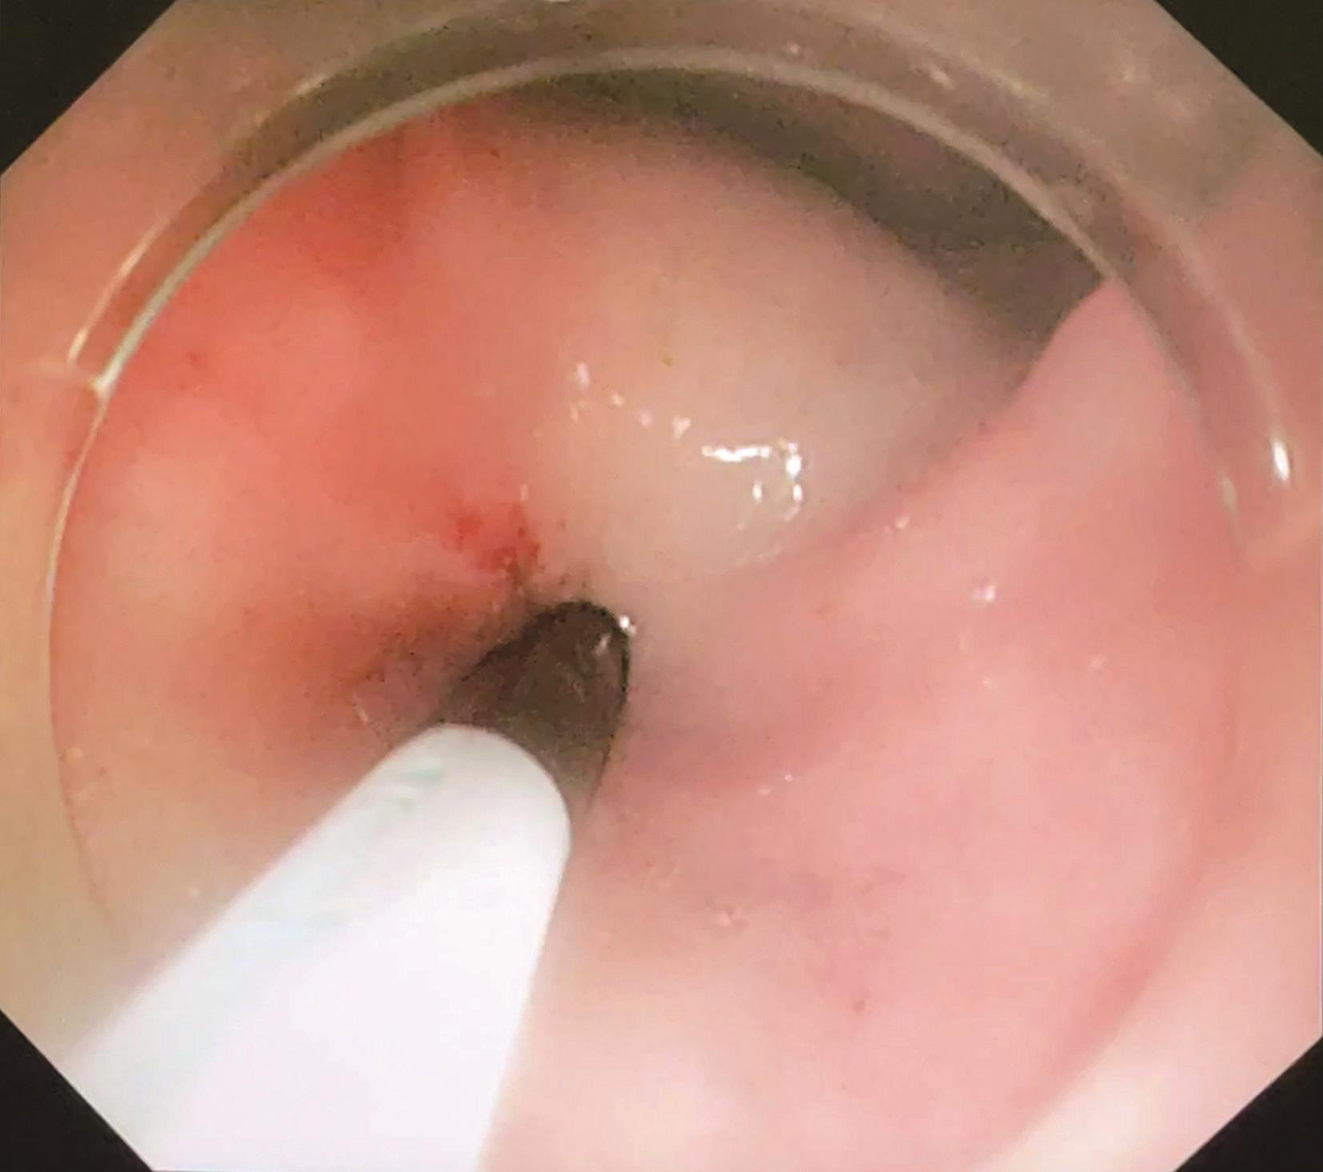

患者于2018年08月30日接受“腹腔镜+胃镜双镜联合胃肿瘤切除术”,胃肠外科与消化科医师共同上台。术中内镜见胃体小弯侧后壁直径4cm黏膜下肿瘤,腔内生长,未侵犯胃黏膜及浆膜(图3),胃周淋巴结无肿大,小网膜囊内可及直径1cm钙化脂肪结节一枚,肝脏、盆腔、腹膜未及转移灶。经口置入内镜,探查肿瘤,于肿瘤边缘黏膜下注水(图4);内镜指引下,腹腔镜下以超声刀距肿瘤边缘1cm切开胃壁浆膜,沿肿瘤包膜外,全层切开胃壁,完整切除肿瘤(图5);以3-0可吸收线间断全层缝合胃壁缺损;术中胃镜检查胃创面;创面部分黏膜缺损处内镜下以钛夹封闭(图6);肿瘤标本置于标本袋内,经脐部戳孔处取出(图7)。

图3 术中内镜探查肿瘤